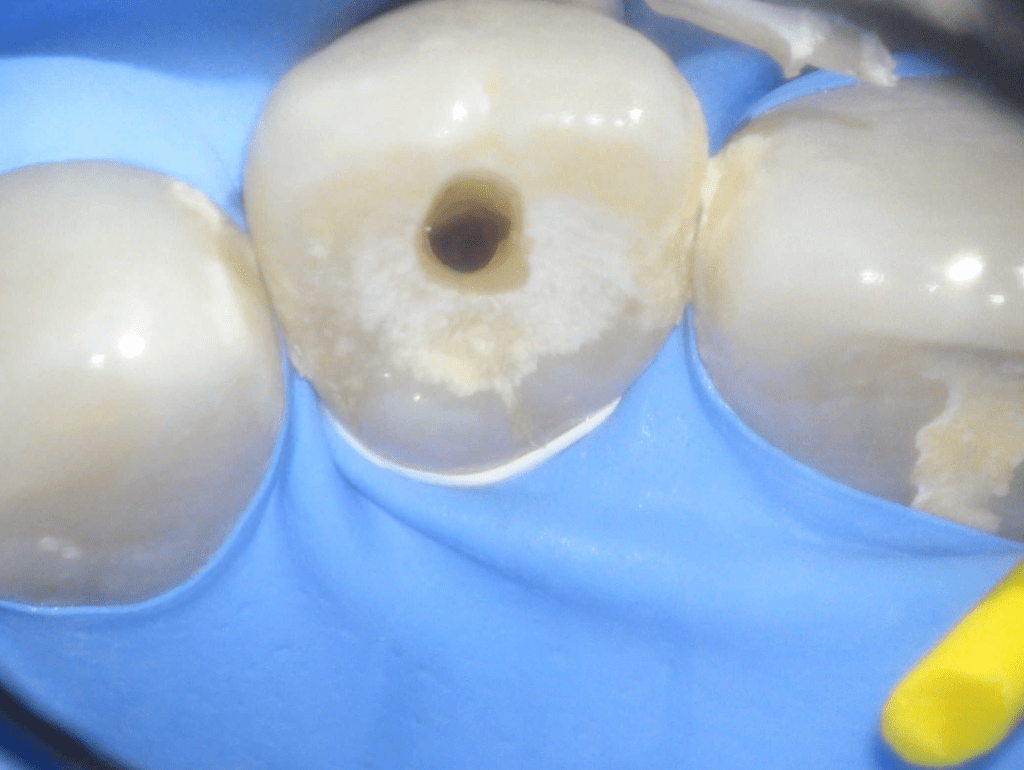

Fractura con exposición pulgar

Reconstrucción con recubrimiento pulgar indirecto